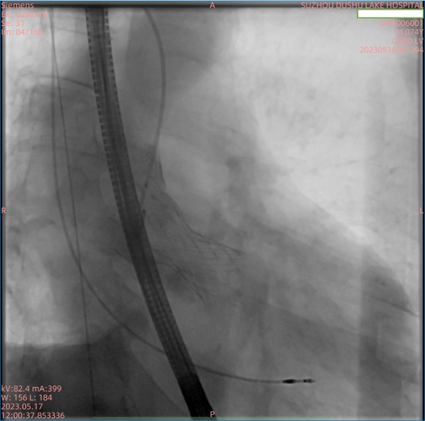

患者为74岁男性,因“反复胸闷1年余,加重1周”入住我院心内科病房。入院后完善心脏彩超,根据结果诊断为主动脉瓣重度狭窄。此次手术选用园区某生物医药公司自研的瓣膜,术前跨瓣压差测得68mmHg左右,术后即刻跨瓣压差小于5mmHg,手术效果较好。

主动脉瓣狭窄(AS)是因老年性瓣膜退行性改变、风湿性心脏病及先天性原发病导致主动脉瓣钙化、粘连,进而发展为瓣口狭窄。有症状及伴有心力衰竭的AS患者预后极差,未经治疗,50%患者生存期少于2年。治疗方式主要有外科瓣膜置换及经导管瓣膜置换。相比于传统开胸体外循环下的主动脉瓣置换,TAVR免于传统外科手术所产生的正中开胸的损伤,不经历一系列包括体外循环、心脏停跳、心脏复跳等步骤,减少了创伤及手术风险。TAVR手术仅行双侧腹股沟穿刺,手术时间、术后恢复、住院时间均较短。